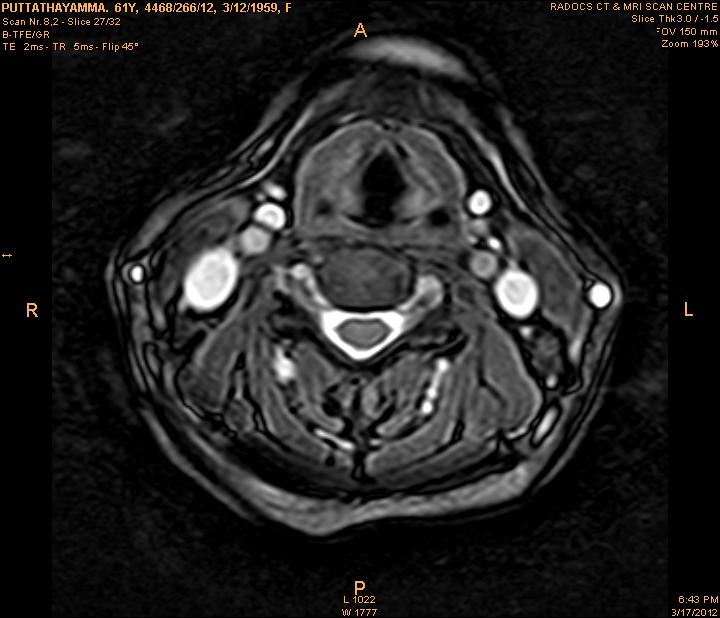

The developed algorithm presented in the previous section was coded using Matlab Version 8.0. The experiment was conducted by considering poor quality spinal cord images of having various lesions. The first column of Fig. 4 shows the axial view of neck spinal cord images of size pixels, respectively. The second column of Fig. 4 presents the same images enhanced using histogram equalization. As is evident from the results presented, the histogram equalization method performs global image enhancement operation which improves the contrast of an image but at the cost loss in image details. The third column of Fig. 4 shows the MSR based spinal cord image enhancement. It can be seen that from the result presented, MSR scheme improves the details that are not clearly visible in histogram equalization technique. In general, image enhancement achieved by MSR method is better compared to histogram equalization. However, the MSR method voilates gray world assumption. Therefore, the image enhanced by this scheme appears to be grayish. Although, numerous work have been reported for solving the problem due to gray world voilation, no work seems to developed for complete elimination.

The fourth column of Fig. 4 shows the image enhanced using Chao et al. []. It can be seen from the results presented that the reconstructed images of Chao’s method have black spots. The appearance of these dark patches degrades the visual quality of the enhanced image. The image enhanced using proposed multirate multiscale retinex image enhancement method presented in the fifth column of Fig. 4, overcomes the drawback of the Chao’s method. As we can see from the simulation results, image enhancement achieved by the proposed method has improved details with significant contrast enhancement. The enhanced images from the proposed method provides information to physicians, radiologists and researchers for various types of pathology detection.